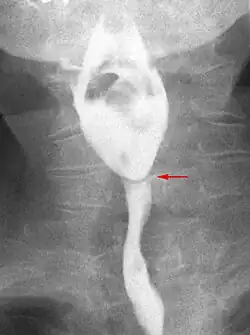

Esophageal web stenosis in barium swallow examination frontal view.